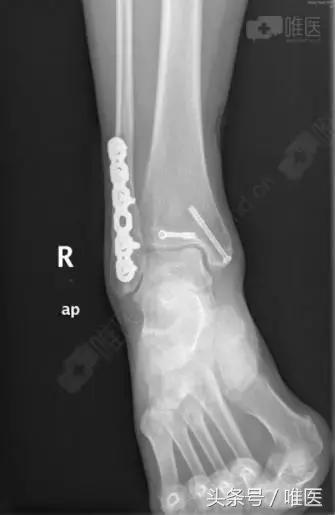

治疗后影像

手术名称:右踝关节骨折切开复位内固定术。

全身麻醉成功后,取左侧卧位,右下肢常规消毒铺巾,右外踝后外侧切口长约8cm切开皮肤、深筋膜,自拇长屈肌及腓骨长短肌间隙进入,暴露外踝及后踝骨折块,复位后踝骨折块后予克氏针临时固定,纠正腓骨远端骨折外移及短缩畸形,克氏针临时固定,透视外踝及后踝骨折复位良好,取合适长度的后侧解剖锁定钢板螺钉牢固固定外踝,空心螺钉固定后踝,再次透视骨折复位及内固定位置良好,冲洗缝合外侧伤口,取仰卧位,右内踝弧形切口切开暴露内踝骨折块及内侧间隙,术中见内踝骨折移位,内侧间隙内碎骨块游离,清理内侧间隙,复位内踝骨折后予导针固定,透视骨折复位及导针位置良好,取34mm长度的4.0 空心螺钉牢固固定,透视骨折复位及内固定位置良好,冲洗伤口,缝合,术中出血约100ml,未予输血。术中伤口予罗哌卡因+得宝松局部镇痛治疗。手术顺利,病人送PACU。